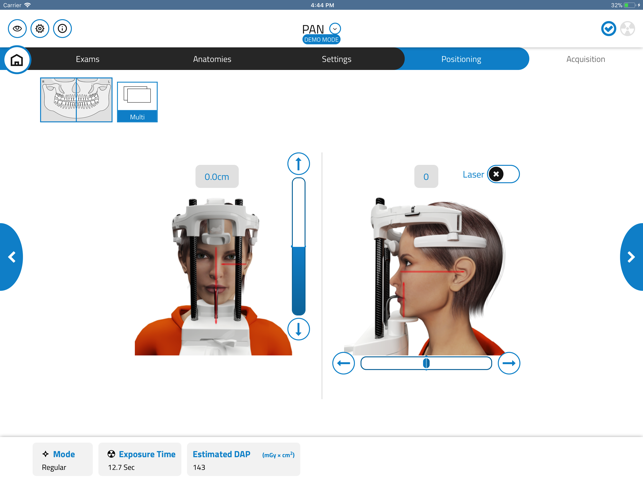

GiANO HR is a highly advanced dental equipment by NewTom, with panoramic, ceph and CBCT capabilities. NewTom Control Pad allows GiANO HR users to connect via Wi-Fi to the equipment, browse the diagnostic programs available, select an imaging modality and a region of interest before performing a radiographic examination.

NewTom Control Pad does not replace any PC workstation, where NewTom NNT imaging software will process and store the radiographic data. Nevertheless, NewTom Control Pad provides quick and easy previewing of 2D radiographs acquired, with image enhancement such as brightness, contrast and gamma correction, as well as e-mailing of 2D images to a preferred recipient.